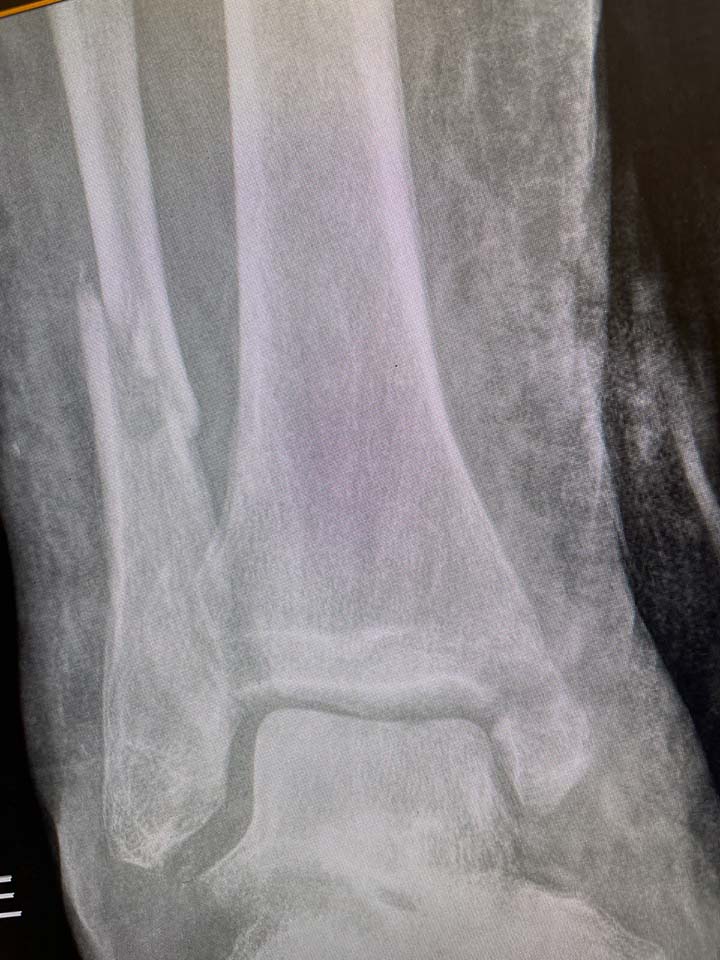

A Minimally Invasive Alternative to Traditional ORIF

In contrast to traditional ORIF of the ankle, Fibunail is inserted in the distal fibula through a minimal stab incision.